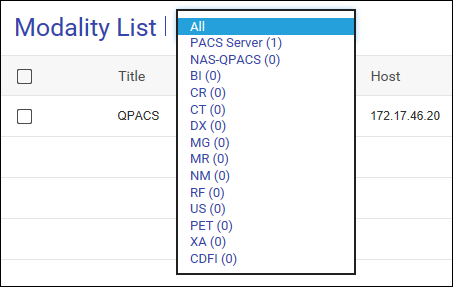

在 MediQPACS 的“AE Management”(AE 管理)屏幕中,用户可以在本地或外部网络上添加、编辑、删除、搜索和测试其他 AE 的连接。

搜索 AE